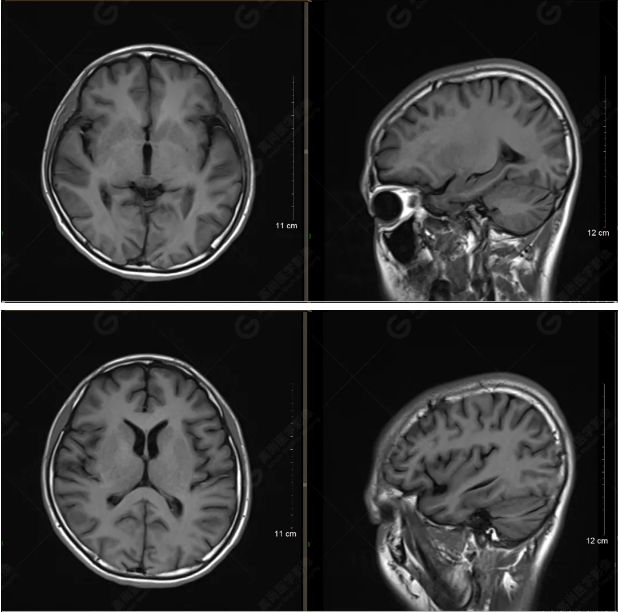

以下是T1WI軸位掃描及矢狀位掃描:

雙側(cè)大腦半球?qū)ΨQ,灰白質(zhì)對比正常,顱內(nèi)未見異常信號影。腦室系統(tǒng)未見擴(kuò)大,中線結(jié)構(gòu)居中。腦溝、裂未見增寬。幕下小腦、腦干未見異常。矢狀位示垂體形態(tài)、大小級信號未見異常。所示左側(cè)乳突內(nèi)見多發(fā)短T1長T2信號影。

顱腦MRI平掃未見明顯異常,左側(cè)乳突內(nèi)積血,建議補充SWI檢查。